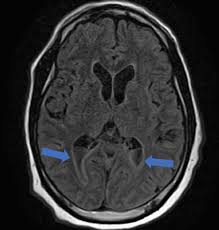

symmetric hyperintensities of putamen > caudate, thalamus, brainstem; red nuclei are eyes

wilson’s disease

from copper deposition